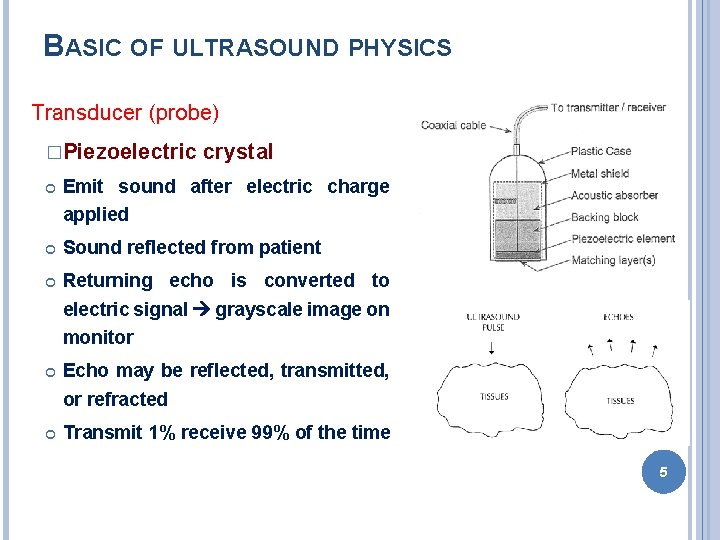

BASIC OF ULTRASOUND PHYSICS Transducer (probe) �Piezoelectric crystal Emit sound after electric charge applied Sound reflected from patient Returning echo is converted to electric signal grayscale image on monitor Echo may be reflected, transmitted, or refracted Transmit 1% receive 99% of the time 5